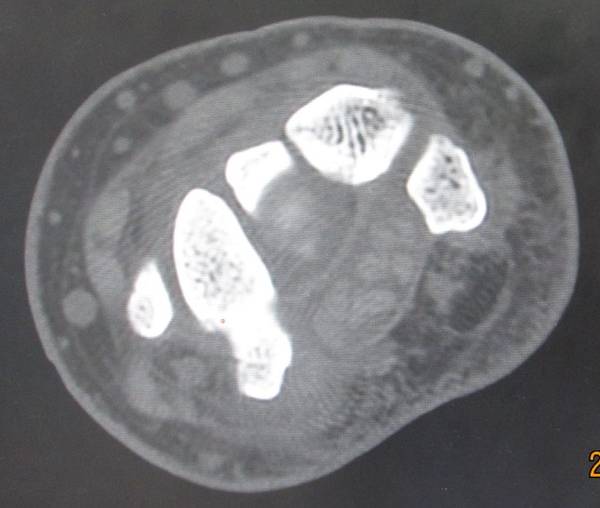

今天去ct室拍了一组舟骨骨图片

在机房看的动态的图像,想怎么看就怎么看

随便转

对骨质结构情况一目了然

太清楚了

舟骨骨折

一侧皮质断裂

平片不明显,幸亏做了CT